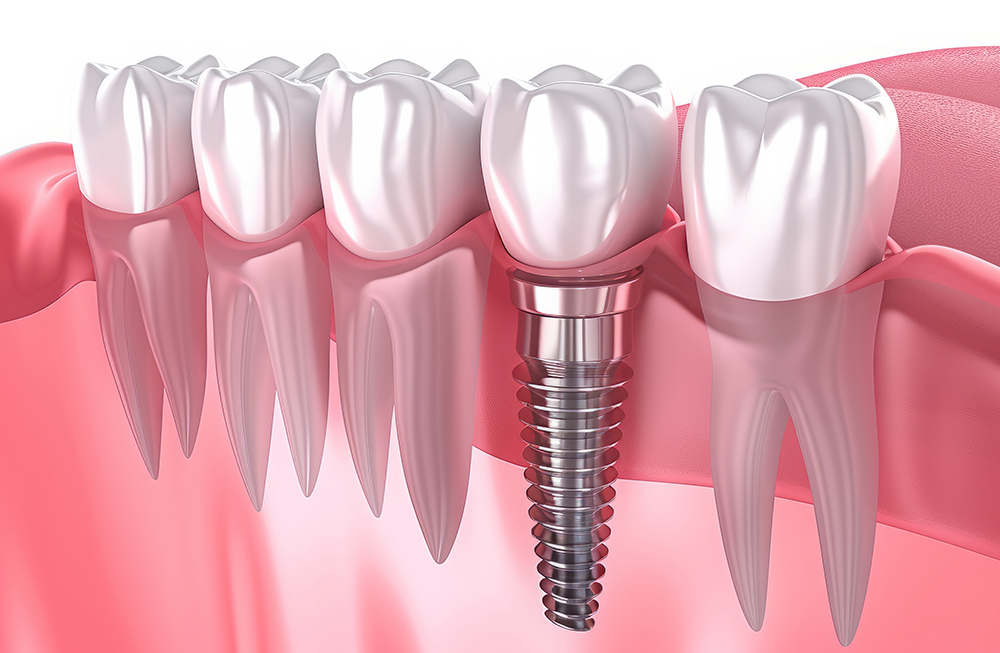

3. 임플란트 식립 수술

본격적인 임플란트 식립 과정에서는 치조골에 인공치아 뿌리(임플란트)를 심습니다. 이 과정은 국소마취를 하며, 수술 시간은 보통 한 개당 30분에서 1시간 정도 걸립니다. 수술이 끝나면 잇몸을 봉합하고, 임플란트가 뼈에 완전히 결합될 때까지 기다려야 합니다.

골유착이 완료되면 임플란트 위에 지대주(어버트먼트)를 연결하고, 그 위에 보철물을 부착합니다. 이 과정에서 환자 맞춤형 치아 모양을 디자인하고 제작하며, 자연치아와 최대한 유사하게 보이도록 조정합니다. 최종적으로 임플란트 보철물을 설치하며, 이로써 전체 시술이 마무리됩니다.